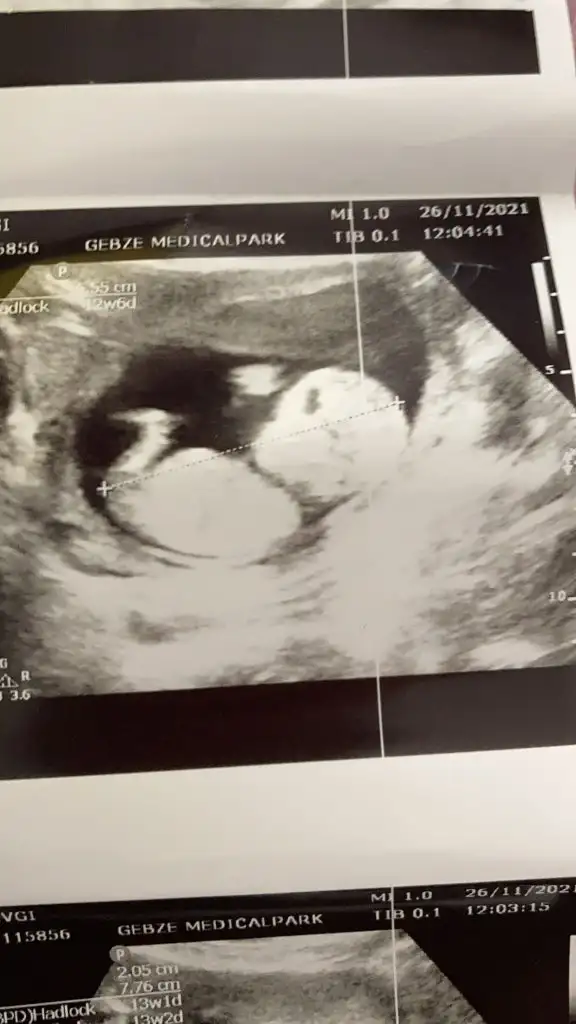

Canım bizde 13 haftalık olduk geldik bakar mısın

Erkek sankiİkra hanım merhaba 12 hafta görüntülerini ekledim sizce nedir cinsiyeti

Erkek ve kız için 11 + 12+ yada 13 hafta usg görüntüsü olmalı açıklamalar asagıda yazıyorrabbim herkesin gönlüne göre nasip etsin inşallah .. ecmain